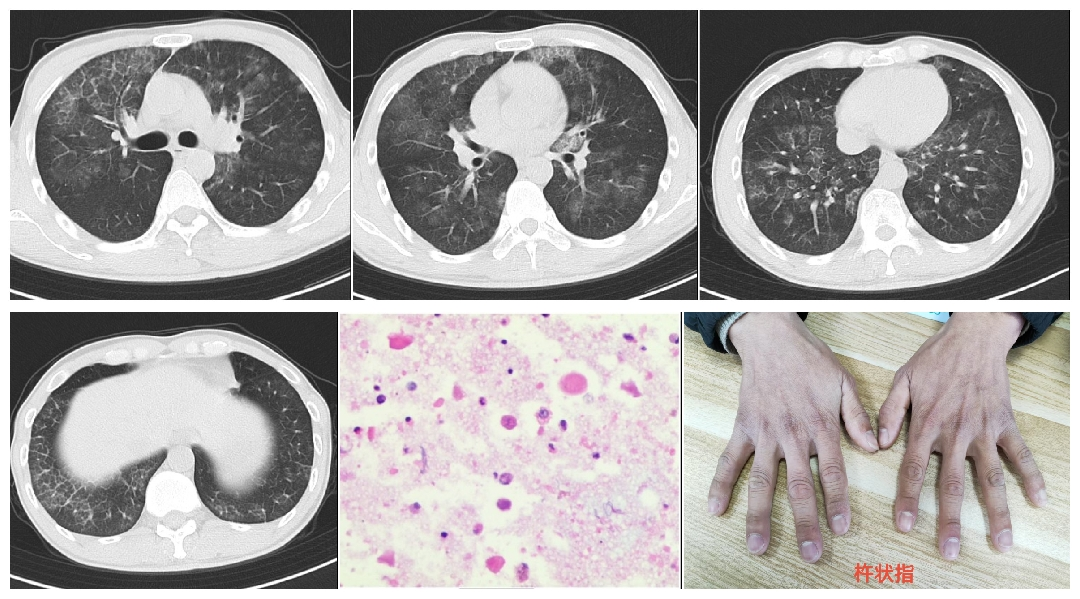

患者因“咳嗽、喘憋2月余”入院,进行性加重,查体发现杵状指,胸部CT显示双肺弥漫性“铺路石征”,犹如双肺被“磨玻璃”覆盖。经支气管镜灌洗及病理检查,确诊为“肺泡蛋白沉积症”。这是一种因肺泡内大量磷脂蛋白样物质异常沉积,导致肺无法有效进行气体交换的罕见病。若不及时干预,将引发严重呼吸衰竭。

由于患者系双侧肺病变,一次性灌洗风险较高,以呼吸重症监护病房冀霞副主任医师、呼吸与危重症医学科一病区康乐主治医师为主的医疗团队决定分期实施“全肺灌洗术”。术中,在静脉复合麻醉下,麻醉医生熟练置入双腔气管插管,实现左、右肺隔离。一侧肺由呼吸机辅助通气,另一侧肺则通过灌洗管反复注入37℃温生理盐水,并轻轻拍打患者胸壁,将沉积在肺泡内的蛋白样物质“洗”出。灌洗液从最初的浑浊“牛奶”样逐渐变为清亮,整个过程持续两个多小时。两次治疗共使用两万多毫升生理盐水,成功清除了沉积在肺泡内的异常物质。

肺泡蛋白沉积症是一种病因未明、会“窒息”的罕见肺部疾病,患病率约为0.2%-0.5%。由于肺泡巨噬细胞功能缺陷,大量富含磷脂的蛋白质样物质在肺泡内沉积,像“水泥”一样堵塞肺泡,阻碍氧气进入血液。患者主要表现为进行性加重的呼吸困难、干咳、胸痛,后期可发展为呼吸衰竭。因症状不典型,早期极易被误诊为肺炎、间质性肺炎等。